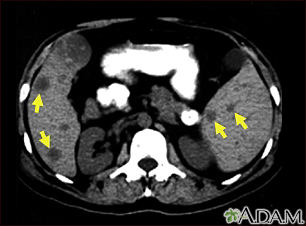

Metastasis is the movement or spreading of cancer cells from one organ or tissue to another. Cancer cells usually spread through the blood or the lymph system.

If a cancer spreads, it is said to have "metastasized."